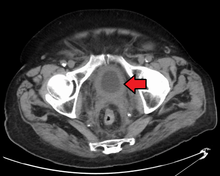

Bladder wall thickening due to cancer

CT Urography shows multiple tumors